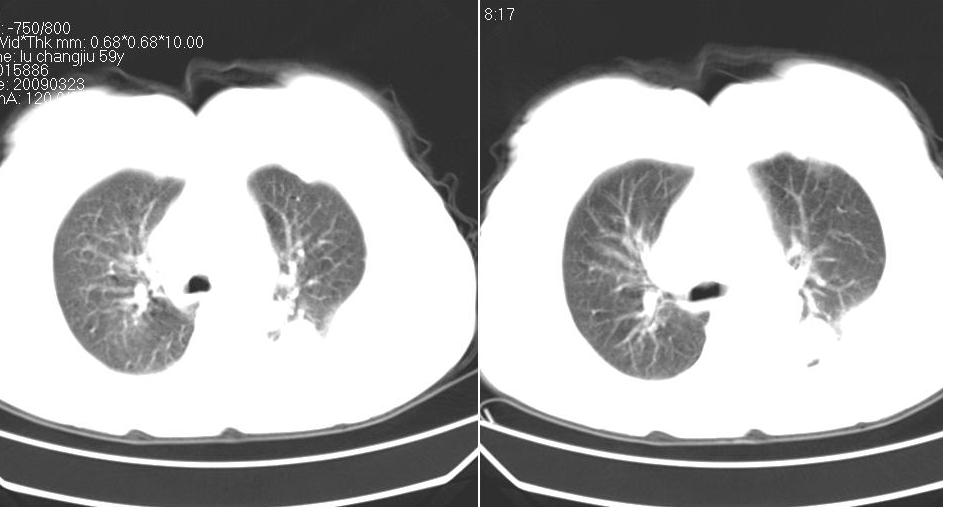

女 59岁,胸背疼,不咳嗽,不咳痰,不发热。

左肺下叶中心性肺癌?tb?;并气胸

1)考虑左肺下叶背段周围型肺癌并左肺下叶及左侧胸膜转移。2)左侧胸腔积液。3)左冠状动脉钙化。

下叶背段也是结核灶多发区,考虑结核可能性大,建议抽胸水检查,肺癌不排除

考虑结核可能性大,建议胸水检查

结核可能性大,建议胸水检查除外占位。

1)考虑左肺下叶背段周围型肺癌(腺癌可能性大)并左肺下叶及左侧胸膜转移。2)左侧胸腔积液。3)左冠状动脉钙化。